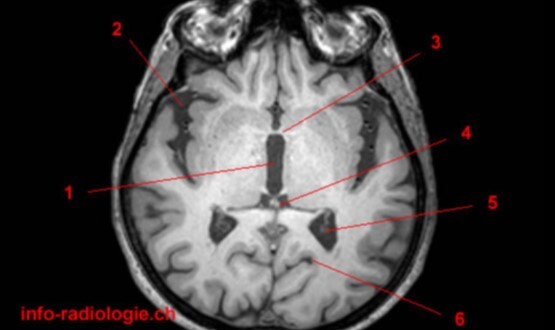

1

Label 1-5

A

1. Rt putamen

2. Rt globus pallidus

3. Rt Caudate nucleus

4. Lt Insula

5. Choroid plexus of left lateral ventricle

2

Label 1-3

1. Rt caudate nucleus

2. Lt lateral ventricle

3. Lt temporal lobe

3

Label 1-4

1. Rt lateral ventricle

2. Lt caudate nucleus

3. Lt lentiform nucleus

4. Lt temporal lobe